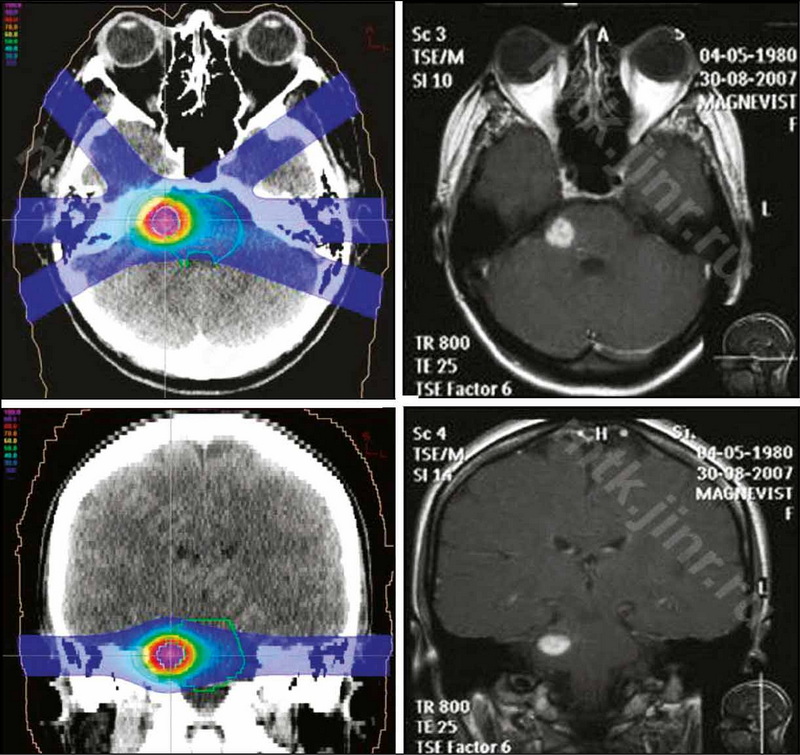

Cavernous malformations of the brain and modern views on their treatment

Abstract

Cavernous malformations of the brain have become an increasingly common pathology in recent years, thanks to the advancement of modern methods of neuroimaging. Despite the benign nature of the course in most cases, these formations can cause convulsions and serious neurological disorders. Typically, clinical manifestations are caused by hemorrhages in the structure of the cavernous and surrounding parenchyma of the brain. The management strategy chosen for patients with cerebral cavernous malformations is determined by the type of malformation, its size, localization, the presence of repeated hemorrhages, and the clinical picture.

This literature review focuses on modern methods of treating cerebral cavernous malformations. The main methods of treatment for cavernous malformations of the brain, particularly surgical treatment, have been analyzed. If surgical intervention is not possible, alternative methods of treatment include radiation therapy, such as stereotaxic radiosurgery, and proton therapy, in cases of deep location of foci in functionally significant areas of the brain, which are characterized by the highest risk of complications. Thе possibilities, efficacy, and safety of stereotactic radiosurgical treatment are discussed, as well as the use of proton therapy in the treatment of cavernous malformations. Furthermore, radiation therapy has been shown to be beneficial for cavernous malformations.

200-210